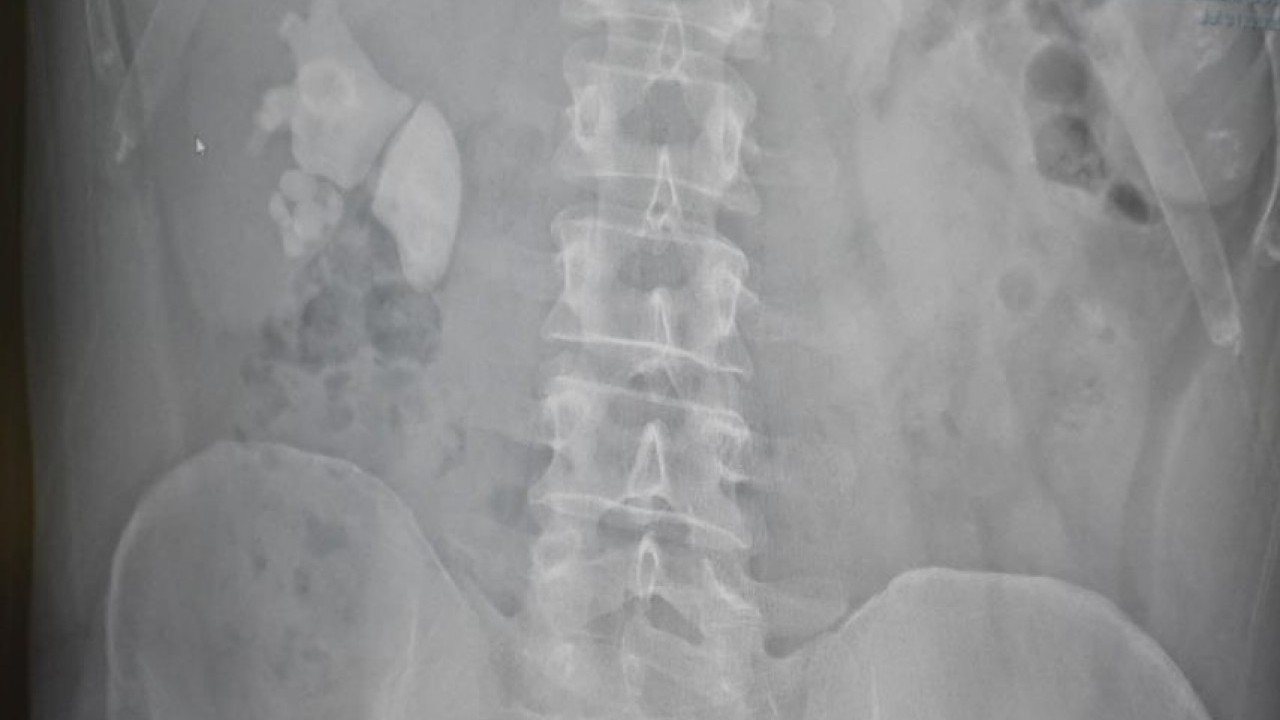

Yozgat’ta yaşayan 45 yaşındaki Serhat Evran’ın böbreğinden 100’e yakın taş çıktı.

Akdağmadeni ilçesinde yaşayan Serhat Evran doktorları bile şaşırtan sağlık problemiyle karşı karşıya kaldı. Şiddetli böbrek ağrısı şikayetiyle Yozgat Şehir Hastanesi’ne başvuran Evran’ın detaylı tetkiklerinin yapılmasının ardından böbreğinde 100 taneye yakın taş tespit edildi.

Ameliyatı gerçekleştiren Op. Dr. Fatih Kocamanoğlu ve Op. Dr. Arif Bedirhan Bayraktar hastanın son durumunu kontrol ederek kısa sürede taburcu olacağını söyledi. Hastanın durumu hakkında açıklama yapan Op. Dr. Fatih Kocamanoğlu hastanın 10 yıl kadar önce sağ böbrekten taş cerrahisi operasyonu geçirdiğini ifade etti. Kocamanoğlu, "Yaptığımız incelemede sağ böbreğin tamamını dolduran taşları vardı.